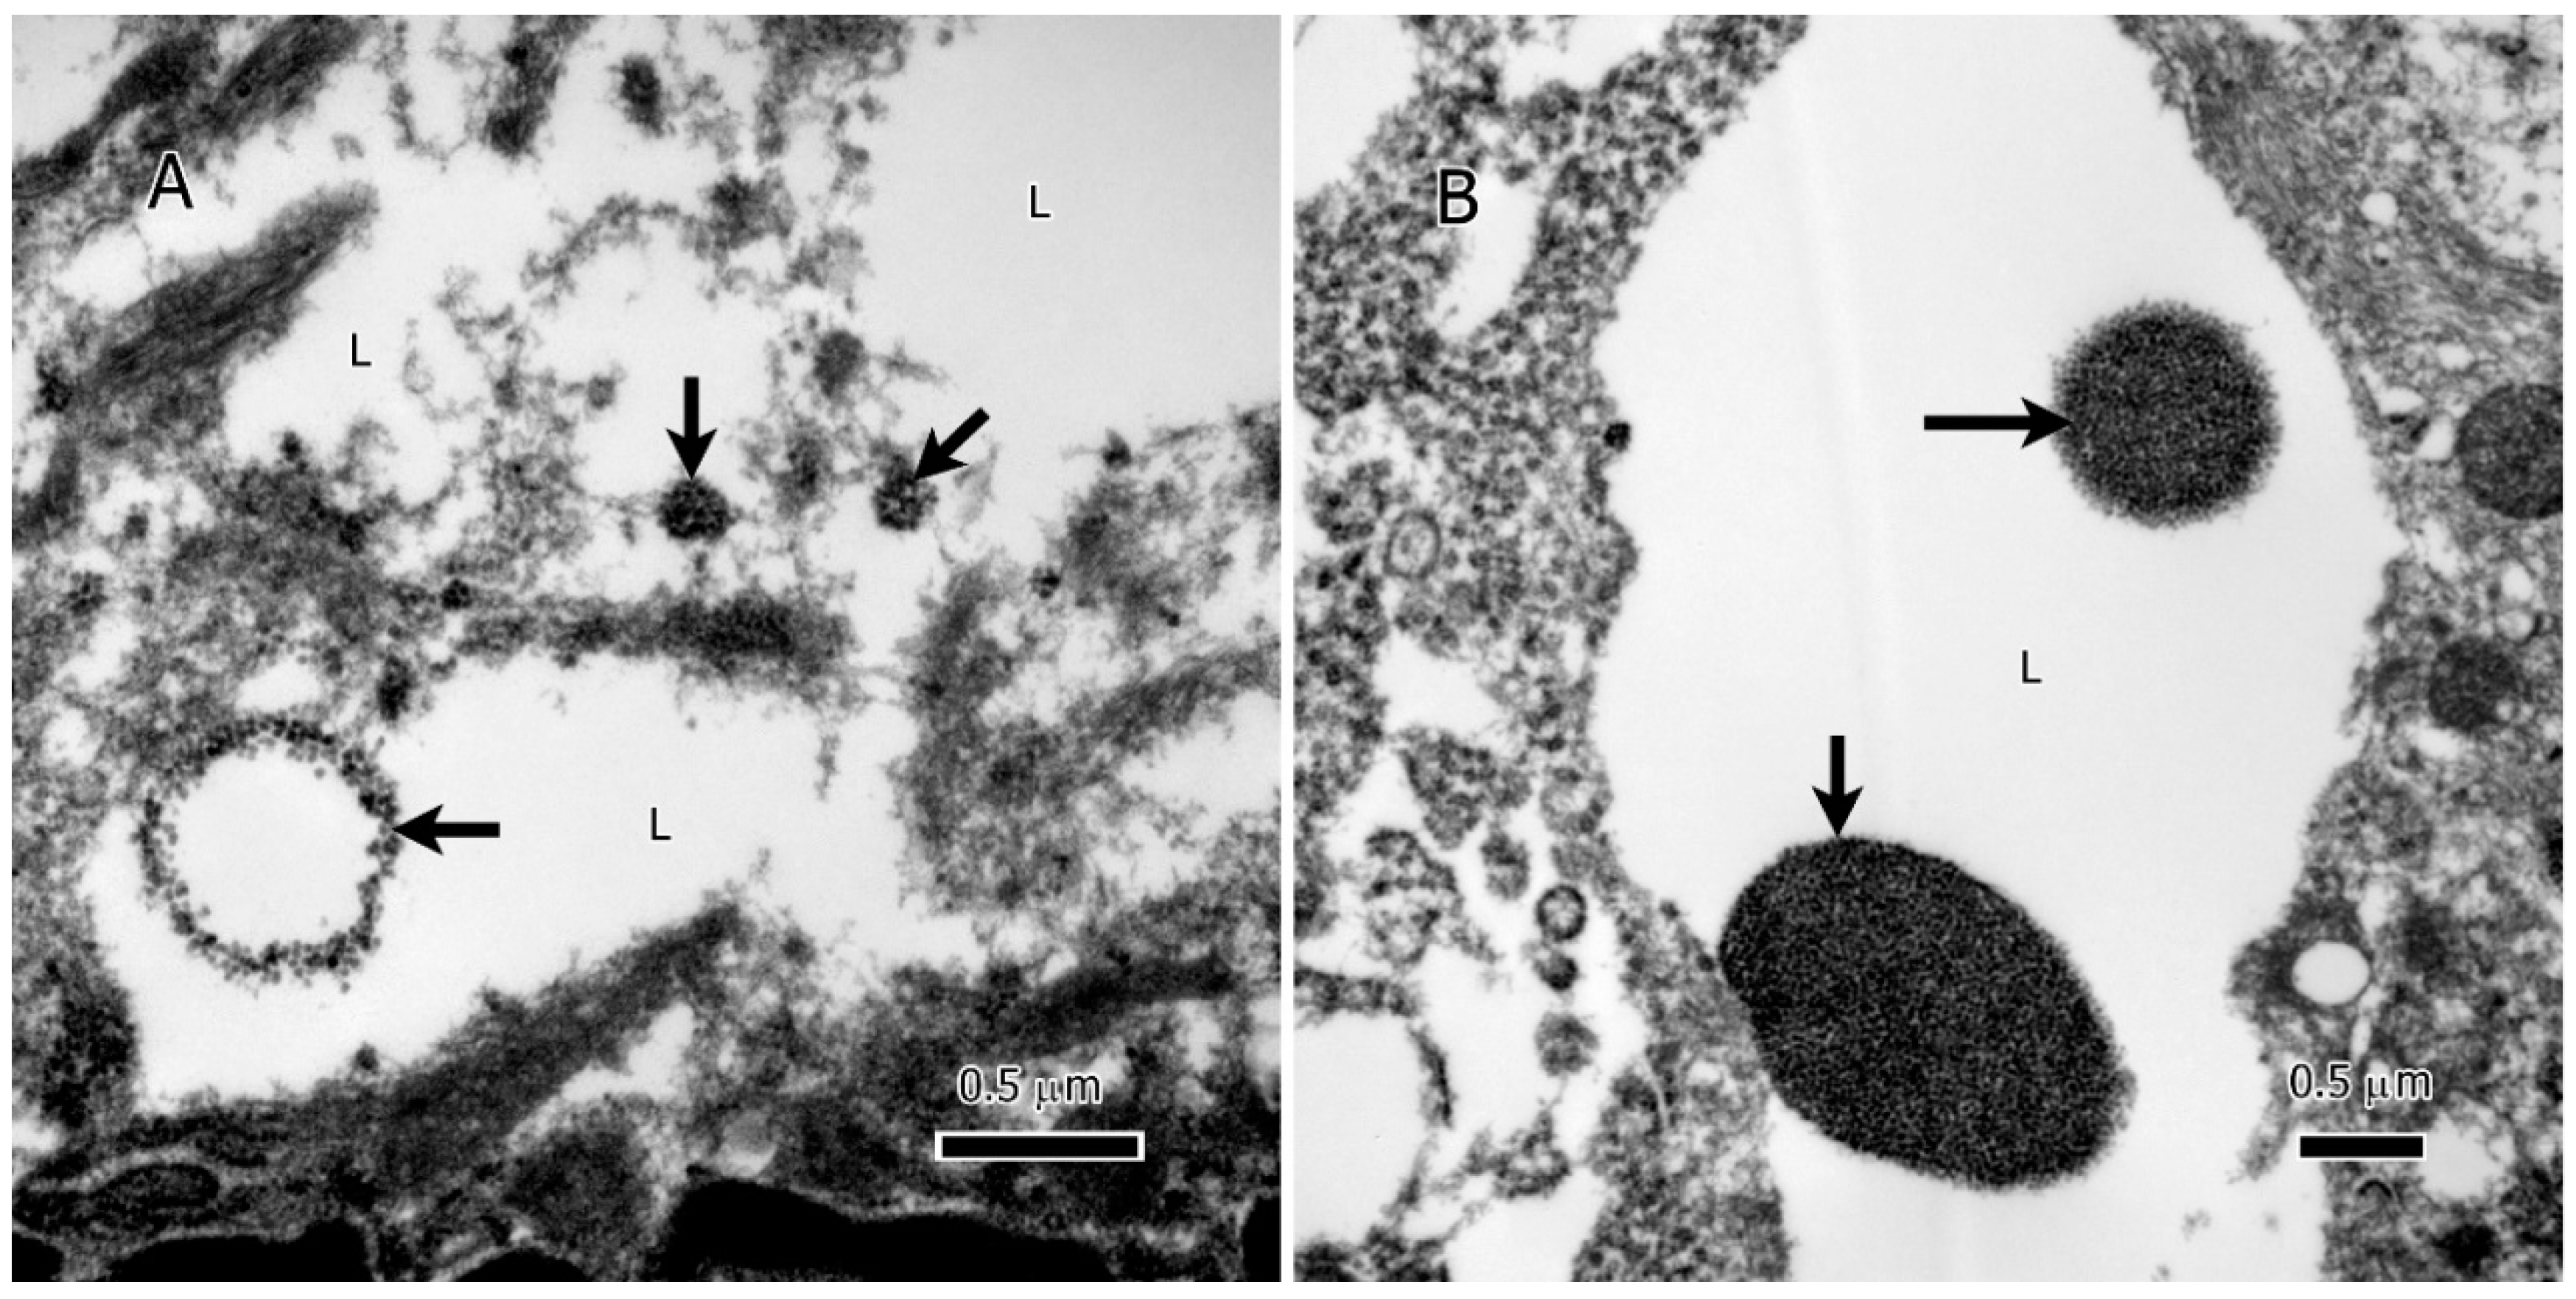

3.1. The State of Lipids in Glioma Tumors

3.2. Lysosomes and Glycogen